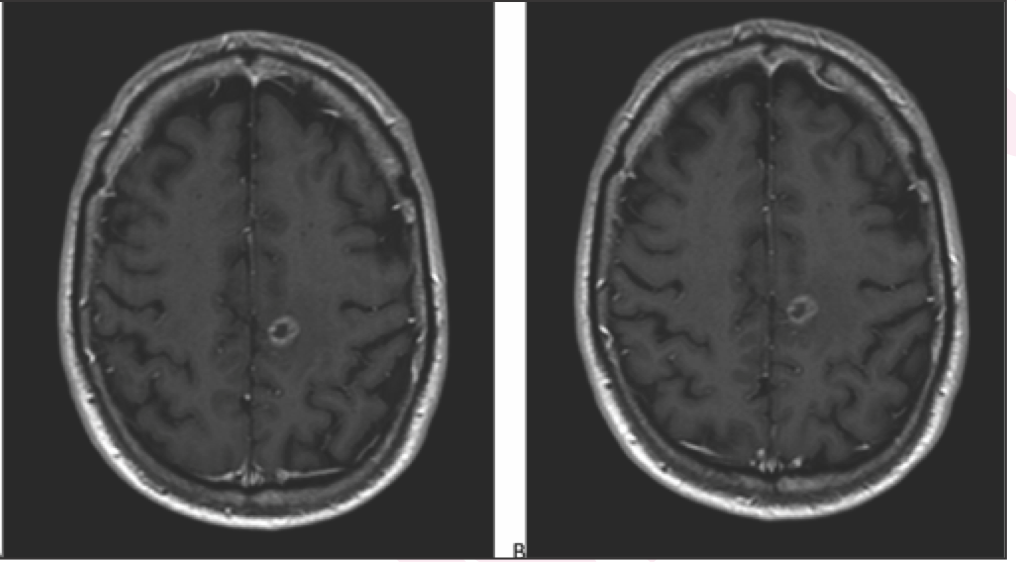

What is your diagnosis on this MRI?